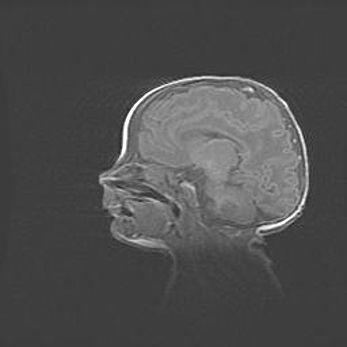

Лейкомаляция с кистозно-глиозной дегенерацией головного мозга.

Возраст: 2 месяца 25 дней

Вес: 6400 г

Окружность головы: 40 см

Срок гестации: 41 неделя

Лейкомаляцию относят к ишемически-гипоксическим повреждениям головного мозга, диагностируемым у новорожденных. При лейкомаляции в головном мозге обнаруживают очаги некроза, возникшие после тяжелой гипоксии и нарушения кровотока. В процессе морфогенеза очаги проходят три стадии: 1) развития некроза, 2) резорбции и 3) формирования глиозного рубца или кисты. Перивентрикулярная лейкомаляция (ПЛ) встречается примерно в 12% случаев среди новорожденных, обычно – у недоношенных детей, причем, частота ее зависит от массы, с которой младенец появился на свет. Наибольшее число малышей страдает лейкомаляцией, если масса при рождении 1500-2500 г.